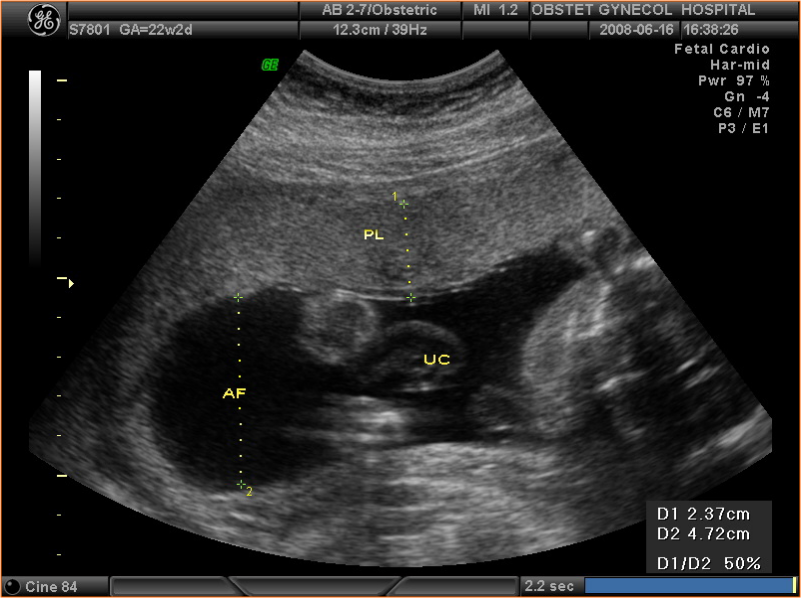

• 4.3 正常中晚期妊娠声像图

正常中晚期妊娠声像图